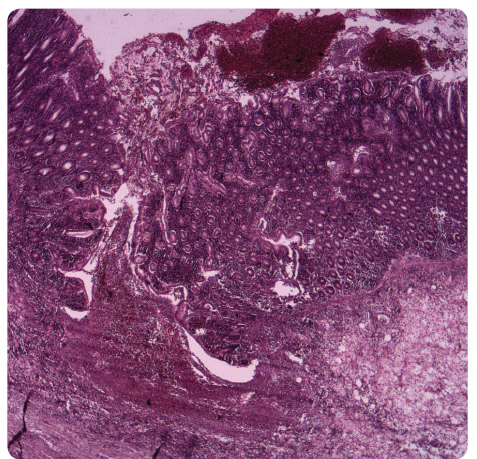

Dne 19. 3. 2009 byl pro silné bolesti břicha, palpační citlivost v levé jámě kyčelní a celkově nelepšící se stav u nemocného proveden kontrolní nativní rtg břicha (obr. 3) – zjištěna další mírná progrese distenze tračníku a nemocný byl přeložen na chirurgickou kliniku k urgentní hemikolektomii. Původně zamýšlená kolonoskopie byla již v této chvíli kontraindikována a gastroenterologové ji odmítli uskutečnit pro nebezpečí perforace střeva. V den překladu provedena subtotální kolektomie s terminální ileostomií. Peroperačně byla prokázána

Obr. 3 Nativní snímek břicha ze dne 19. 3. 2009.těžká pseudomembranózní kolitida, histologicky byla na zastižených preparátech zcela rozrušená struktura sliznice, edém submukózy, rozsáhlé vředy kryté pablánami (obr. 4). Pooperační průběh komplikoval rozvoj A Obr. 4 Histologický preparát z resekovaného tlustého střeva.RDS (syndrom dechové tísně dospělých) v rámci syndromu multiorgánové dysfunkce, který vyžadoval osmidenní pobyt na ARO s UPV (umělou plicní ventilací); odtud byl již stabilizovaný pacient přeložen dne 2. 4. 2009 zpět na chirurgii a záhy propuštěn domů.